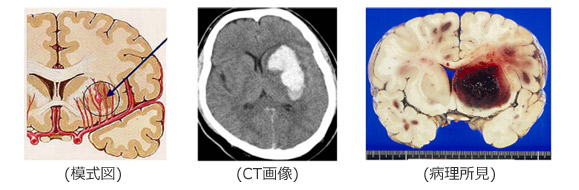

脳出血の原因の多くは高血圧です。高血圧によって脳の血管が動脈硬化性変化をおこし、何らかの拍子に出血したり、下の図のように動脈瘤のように血管が膨らみ、それが破裂して出血することによっておこると言われています。

出血する血管は脳の大きな血管ではなく、下の図のように大きな血管から枝分かれした0.2-0.3mm程度の穿通枝と言われる髪の毛程度の細い血管から出血すると言われています。